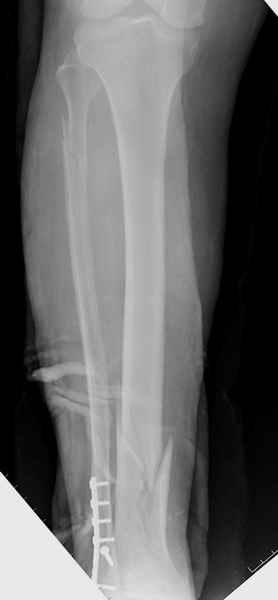

У меня молодой врач на линии, снимки отправил через эл. почту,

спрашивает что делать с больным который поступил недавно, фермер 55 лет падение при пьяной драке в баре, года два назад перенес операцию на лодыжке, на снимках и КТ перелом без вовлечения сустава,

Здесь мы использовали новый Synthes Nail с дополнительными дырками, в проксимальной части 4: по две косых и поперечные (один стандартный а другой динамический), в дистальной части две поперечные, прямая и косая. Вес больного более 120 кг, нагрузку начнем через месяц.